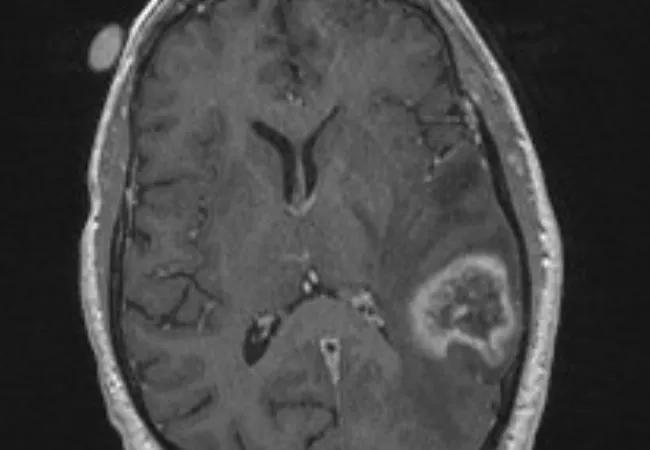

SRS (using Gamma Knife®) offers high rates of local control for brain metastases, but it results in radiation necrosis — confirmed by radiographic or pathologic evidence — in 5 to 10 percent of treated lesions. Half of patients with evident radiation necrosis (as in the imaging study above) develop symptomatic neurological deficits, sometimes requiring prolonged treatment with steroids or anti-angiogenic agents.